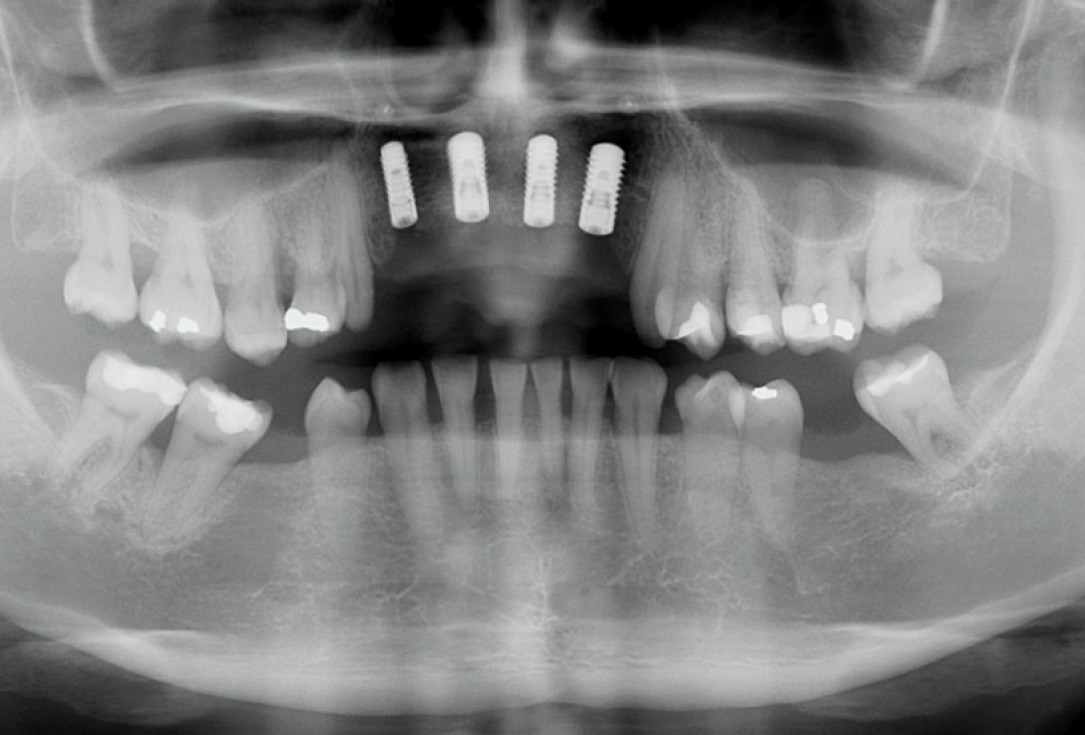

13/17 - X-ray scan after implant insertionRestoration of all four incisors with maxgraft® bonebuilder - Dr. Dr. Dr. O. Blume